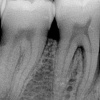

Pöördumatu hambanärvi põletik

Kui algul lihtsalt külmatundlik olnud hammas hakkab valutama järjest tugevamini, siis on tavaliselt tegemist hambanärvi pöördumatu põletiku ehk pulpiidiga.